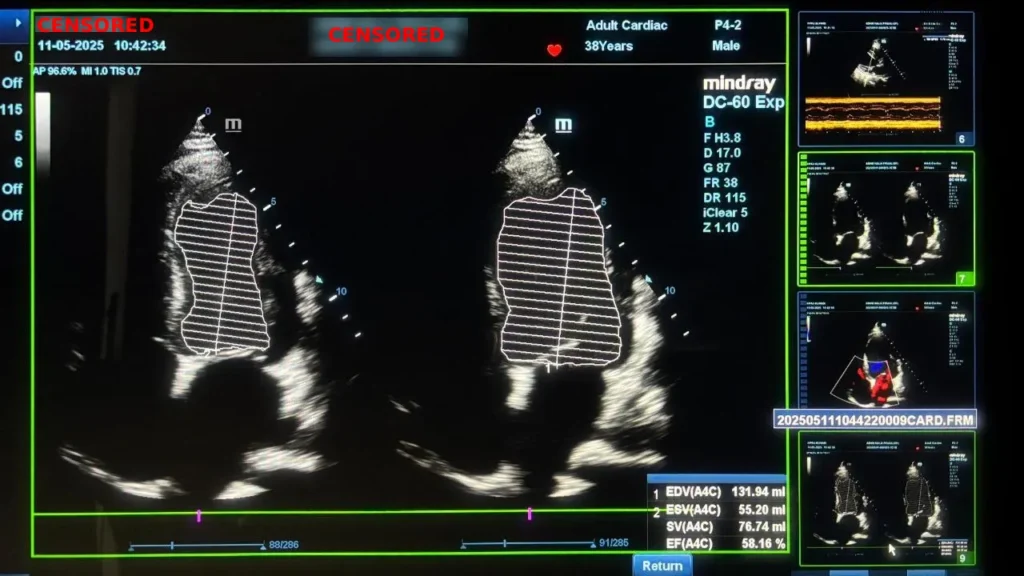

Pasien kemudian memutuskan mengikuti Program CardiacSave dengan pemantauan ketat melalui echocardiografi, laboratorium jantung, dan EKG. Hasilnya sangat menggembirakan. EF meningkat drastis menjadi 58,16 persen, kembali ke rentang normal. Perfusi jantung membaik, gejala kongestif berkurang, dan akumulasi cairan hilang sepenuhnya.

Setelah terapi Program Cardiacsave :

Pada pemeriksaan Echocardiografi EF membaik signifikan menjadi 58,16% (11-05-2025)

Menunjukkan pemulihan fungsi miokardial, peningkatan perfusi jantung, dan perbaikan pompa jantung tanpa prosedur invasif.